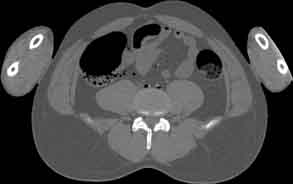

Visible Human male: Sectio transversalis 1731

CT

NMR

Pd                          / T2 \                         T1